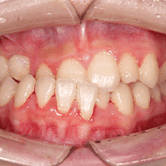

Apiñamiento dental

El apiñamiento dental ocurre cuando no hay suficiente espacio en la mandíbula para que los dientes se alineen correctamente.

Los pacientes pueden notar que sus dientes se superponen y están torcidos. Esta condición puede dificultar la higiene oral y aumentar el riesgo de caries y enfermedades de las encías.

El tratamiento incluye la expansión del arco dental y el uso de brackets.